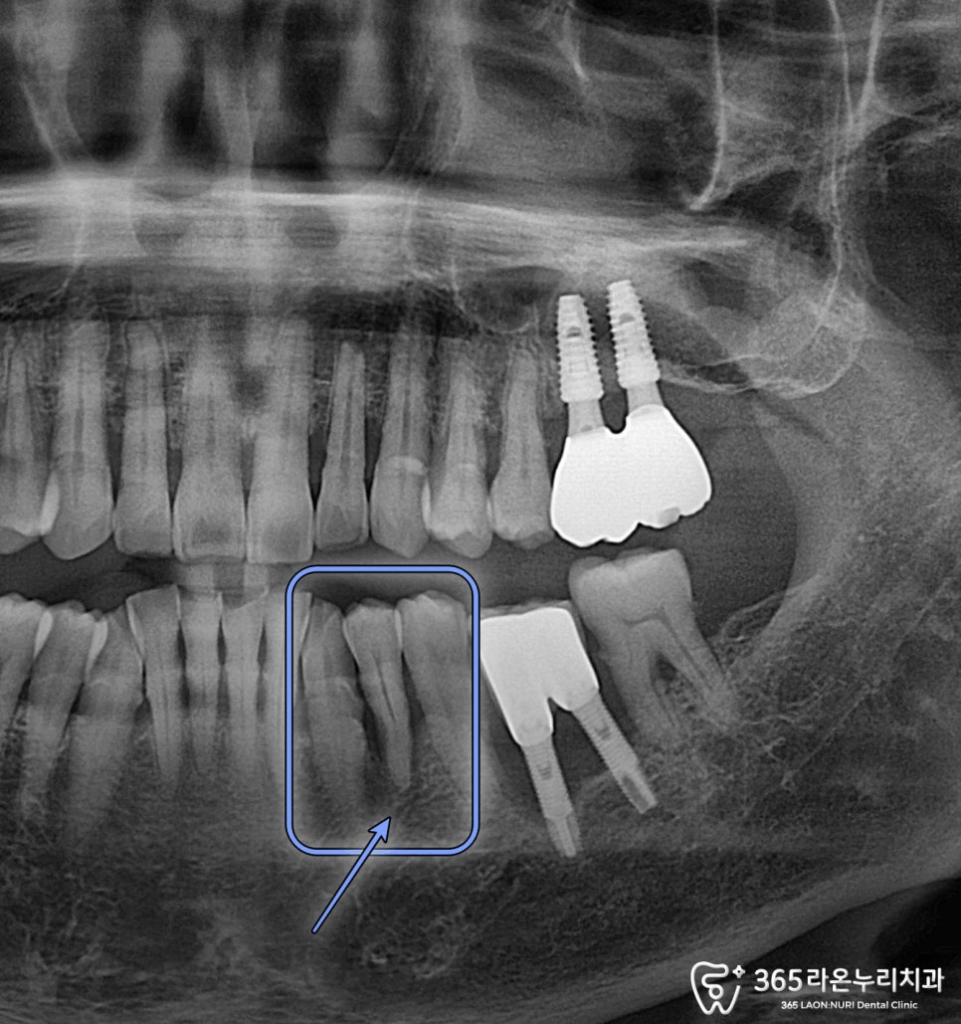

파노라마 엑스레이를

보았습니다.

2025.01.02

치주염으로 치근단 염증 즉, 뿌리 주변으로

염증이 크게 번져가고 있었는데요.

표시해 드린 것처럼 염증이 크게 번지면서

치조골 및 치은이 크게 내려간 것을 알 수 있었죠.

(치조골/치은 퇴행)